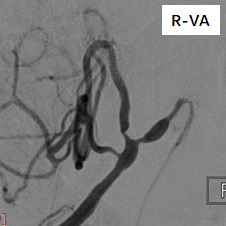

慕璐岩教授专栏丨颅内动脉狭窄治疗集锦